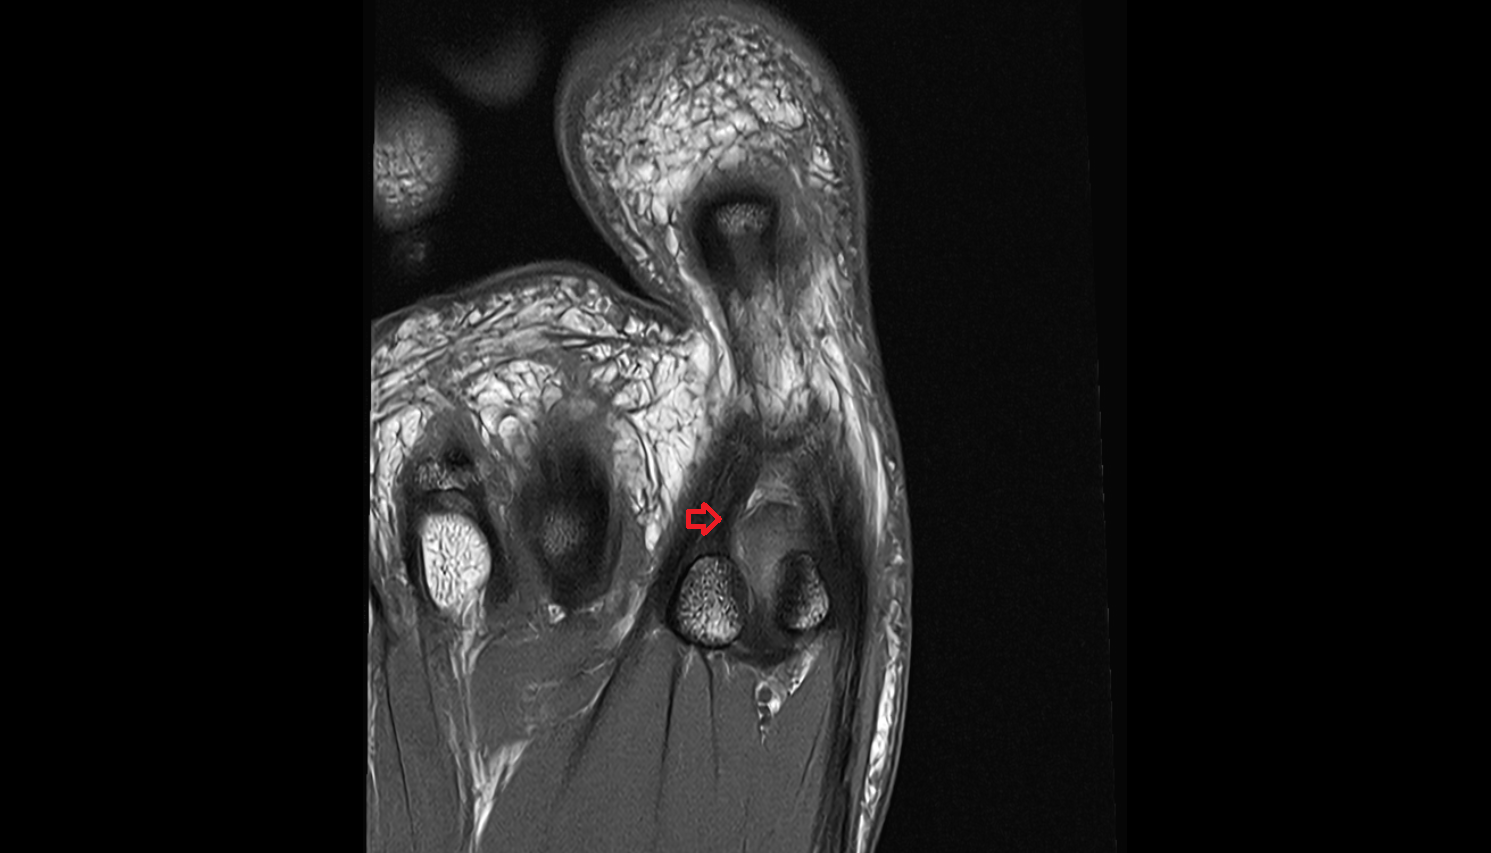

- Sesamoid bone of great toe

- Lateral sesamoid bone

- Medial sesamoid bone

- Intersesamoid ligament